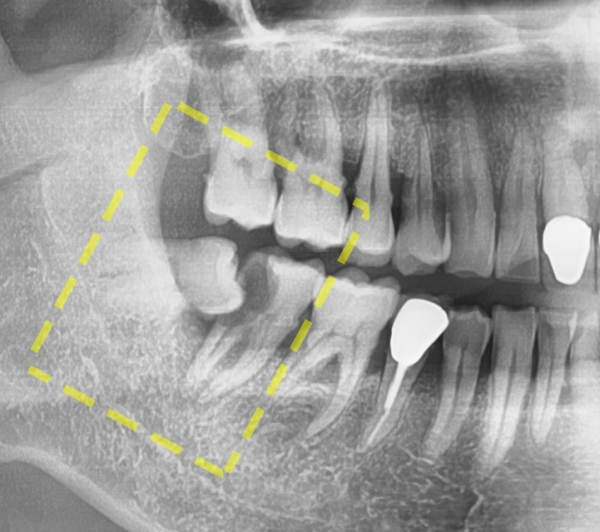

조금더 확대한 사진을 보면 누워있는 사랑니와

바로 앞에 인접한 어금니 사이에 충치가 생겨서 상당히 통증이 느껴질법한 상태였습니다.

이 환자분의 어금니 충치는 심각한 상태였기 때문에 결국 발치 후 임플란트를 하게되었습니다.

환자분의 입장에서는 사랑니때문에 치과를 찾았는데

임플란트까지 해야 한다고 하여 당황스러우실 수 있는 상황이었습니다.

If you look at the enlarged picture, the wisdom tooth lying down

I had a cavity between the adjacent molars right in front of me, so I felt a lot of pain.

This patient's molar cavity was in a serious condition, so he eventually got an implant after extraction.

From your point of view, he went to the dentist because of his wisdom teeth

It was a situation where you could be embarrassed because you had to get an implant.